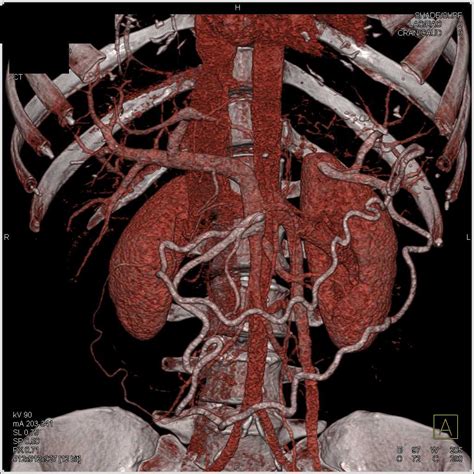

In addition to standard CT scans, advanced imaging techniques can provide even more detailed information about pancreatic adenocarcinoma. These techniques include:

• Magnetic Resonance Imaging (MRI): MRI uses magnetic fields and radio waves to create detailed images of the body. It can provide more information about soft tissues and is often used in conjunction with CT scans.

• Positron Emission Tomography (PET) Scan: A PET scan uses a radioactive tracer to highlight areas of high metabolic activity, which can indicate the presence of cancer cells. It is often combined with a CT scan (PET/CT) to provide both functional and structural information.

• Endoscopic Ultrasound (EUS): EUS involves inserting a thin, flexible tube with a camera and ultrasound probe into the digestive tract to get a close-up view of the pancreas. It can be used to guide biopsies and provide detailed images of the pancreas.

These advanced imaging techniques can complement the information provided by a Pancreatic Adenocarcinoma CT Scan, helping to create a comprehensive picture of the cancer's extent and characteristics.